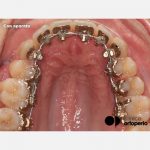

Tratamiento

Se cementaron ambas arcadas el mismo día. Aunque se había previsto utilizar biteplanes en los caninos para abrir la mordida, se decidió colocar además planos de levante de composite en las cúspides de los primeros molares superiores para minimizar el riesgo de despegamiento de brackets. Una mejor opción hubiera sido diseñar el aparato con Half-occlusal pads en los segundos molares superiores e inferiores. Se realizó stripping en la arcada inferior. En la arcada superior se colocó un arco de .014” Nitinol™ SE en el slot de todos los brackets con ligadura metálica simple. En la arcada inferior se colocó un arco de .012” Nitinol™ SE en el clip de autoligado en todos dientes. (Fig. 3).

Un mes después fue posible insertar el .016” Nitinol™ SE en la arcada superior. Se colocó un lasso para ayudar a corregir la rotación del 22. En la arcada inferior se mantuvo el mismo arco, ligándolo esta vez en el slot. Probablemente el segundo arco fino de niti no hubiera sido necesario en la arcada superior. (Fig. 4).